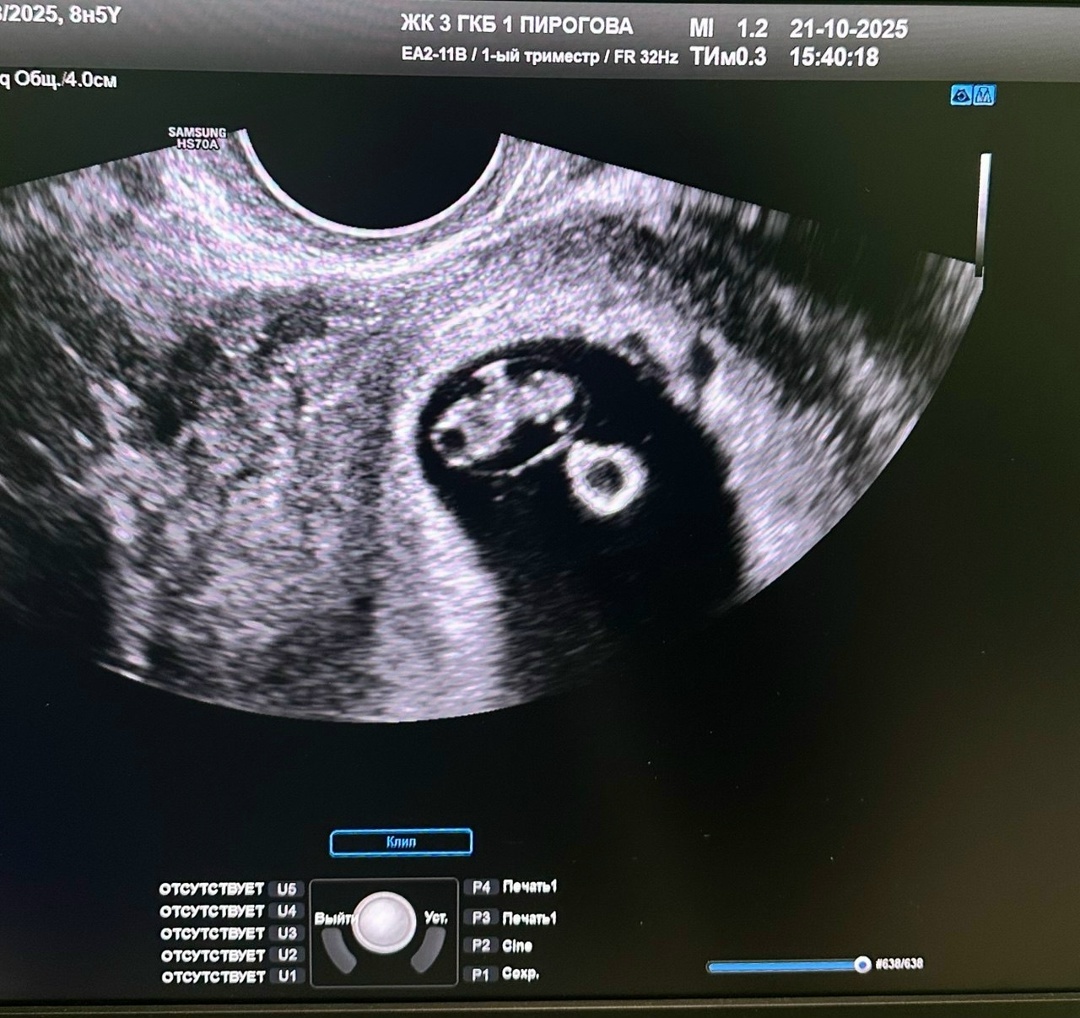

Это, пожалуй, самый волнительный момент. Первое УЗИ обычно делают на сроке 6–8 недель — именно после него, когда врач подтвердит сердцебиение, вас официально поставят на учёт. Ребёнок внутри вас еще не принял привычные нам очертания. Пока там — только крошечное плодное яйцо. Если повезёт, то вы услышите сердцебиение малыша! Сердце бьётся — и от этого сразу становится теплее на душе.

Что проверит врач:

• что беременность развивается в матке (исключит внематочную);

• сколько эмбрионов (да, бывает и не один!);

• есть ли сердцебиение — это ключевой момент для постановки на учёт;

• какой примерный срок — иногда он немного отличается от расчёта по месячным.